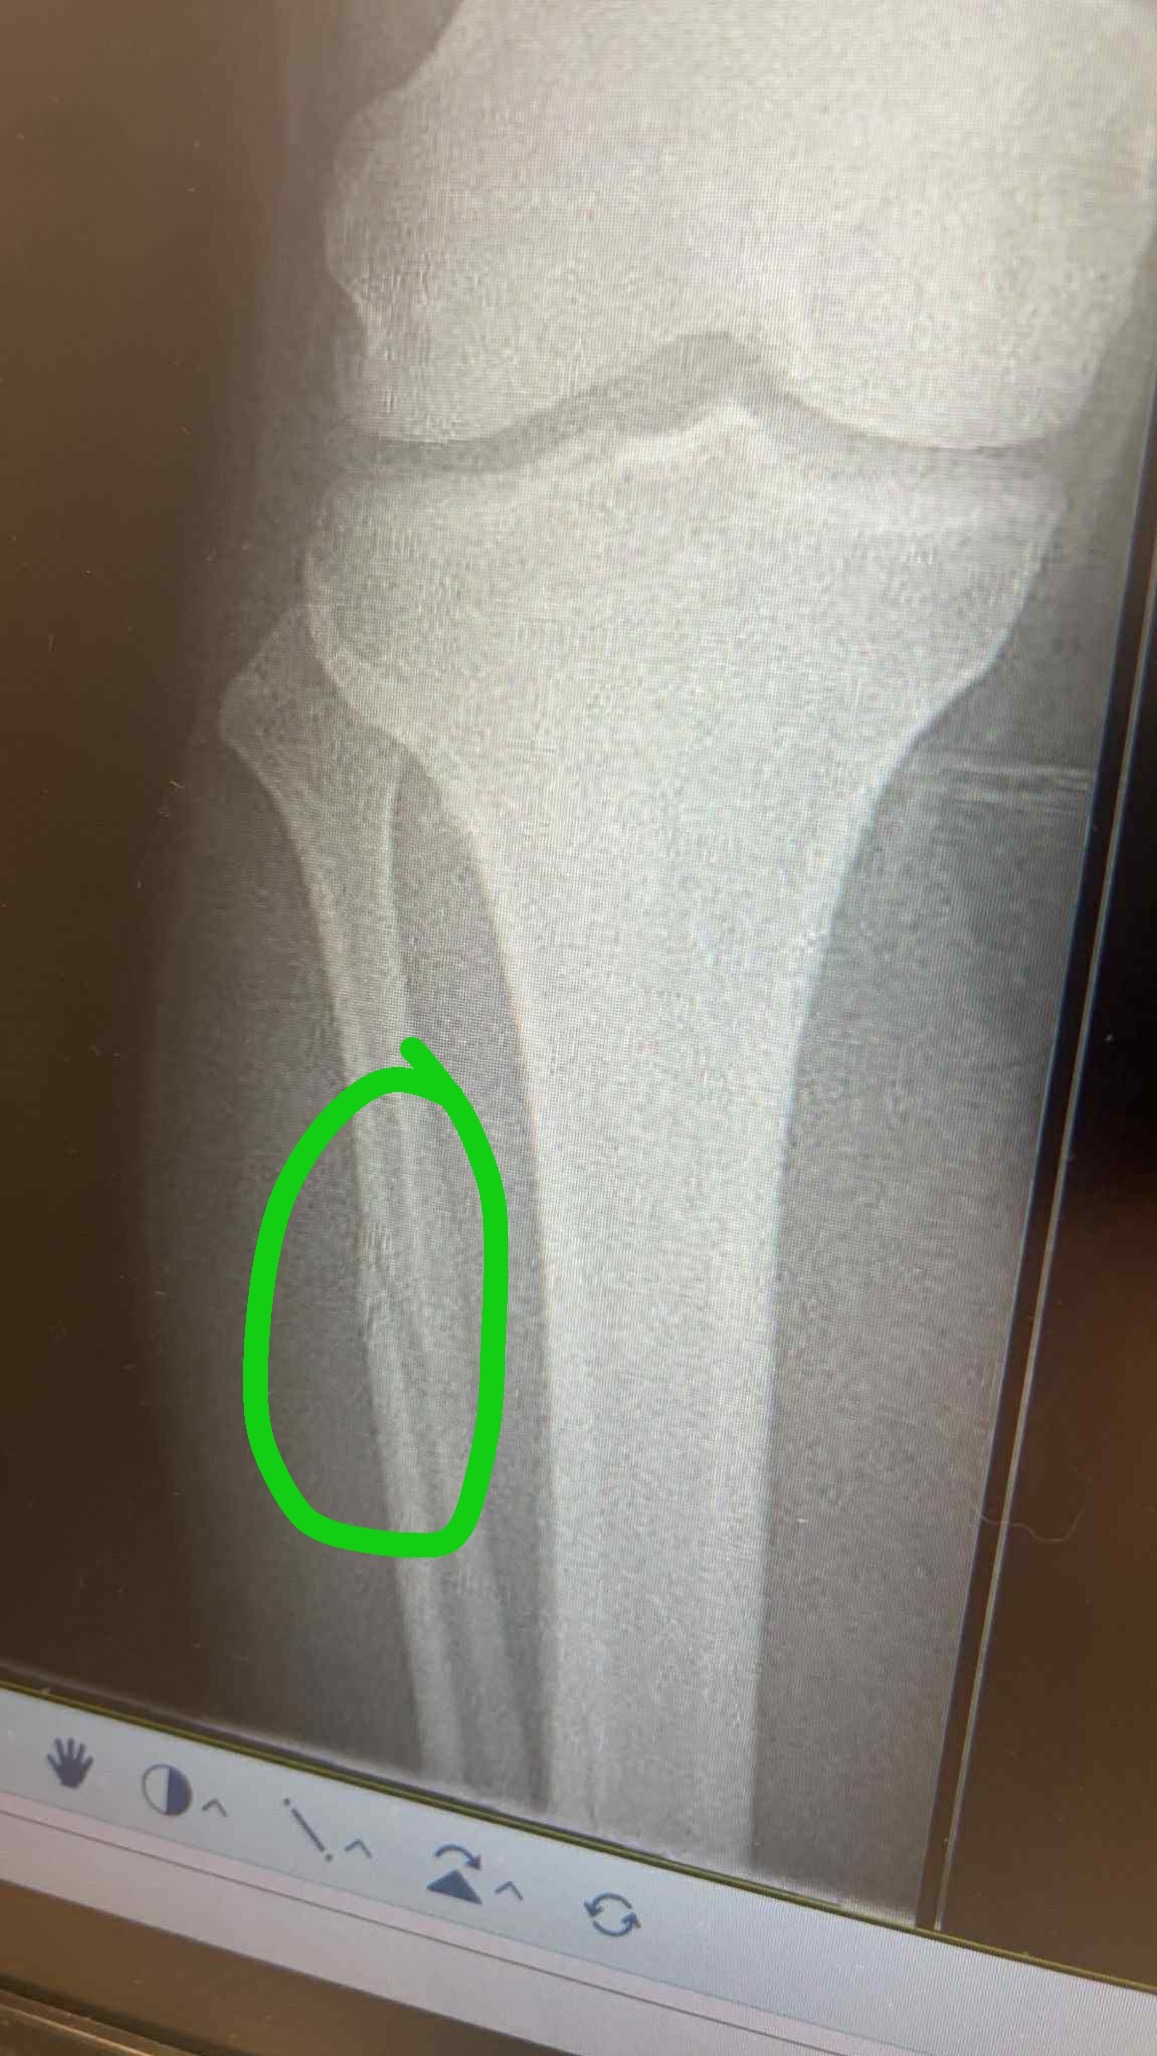

On Saturday 25th October, one of our men’s teams were playing a league match against Montpellier Reserves. During this match one of our players, Josh Swales, unfortunately suffered a triple leg fracture during a horrific tackle. The match was abandoned and Josh was rushed to hospital. In hospital Josh was put into a cast and transferred to Gloucester Royal Hospital. On Monday 27th October, Josh had surgery to insert a metal rod and 4 screws into his leg. On Thursday 30th October, Josh was discharged with crutches to continue recovery from home. He was told he would be unable to put full weight through the leg for at least 6 weeks, be off work for 8-12 weeks and out of any exercise for 4-6 months.